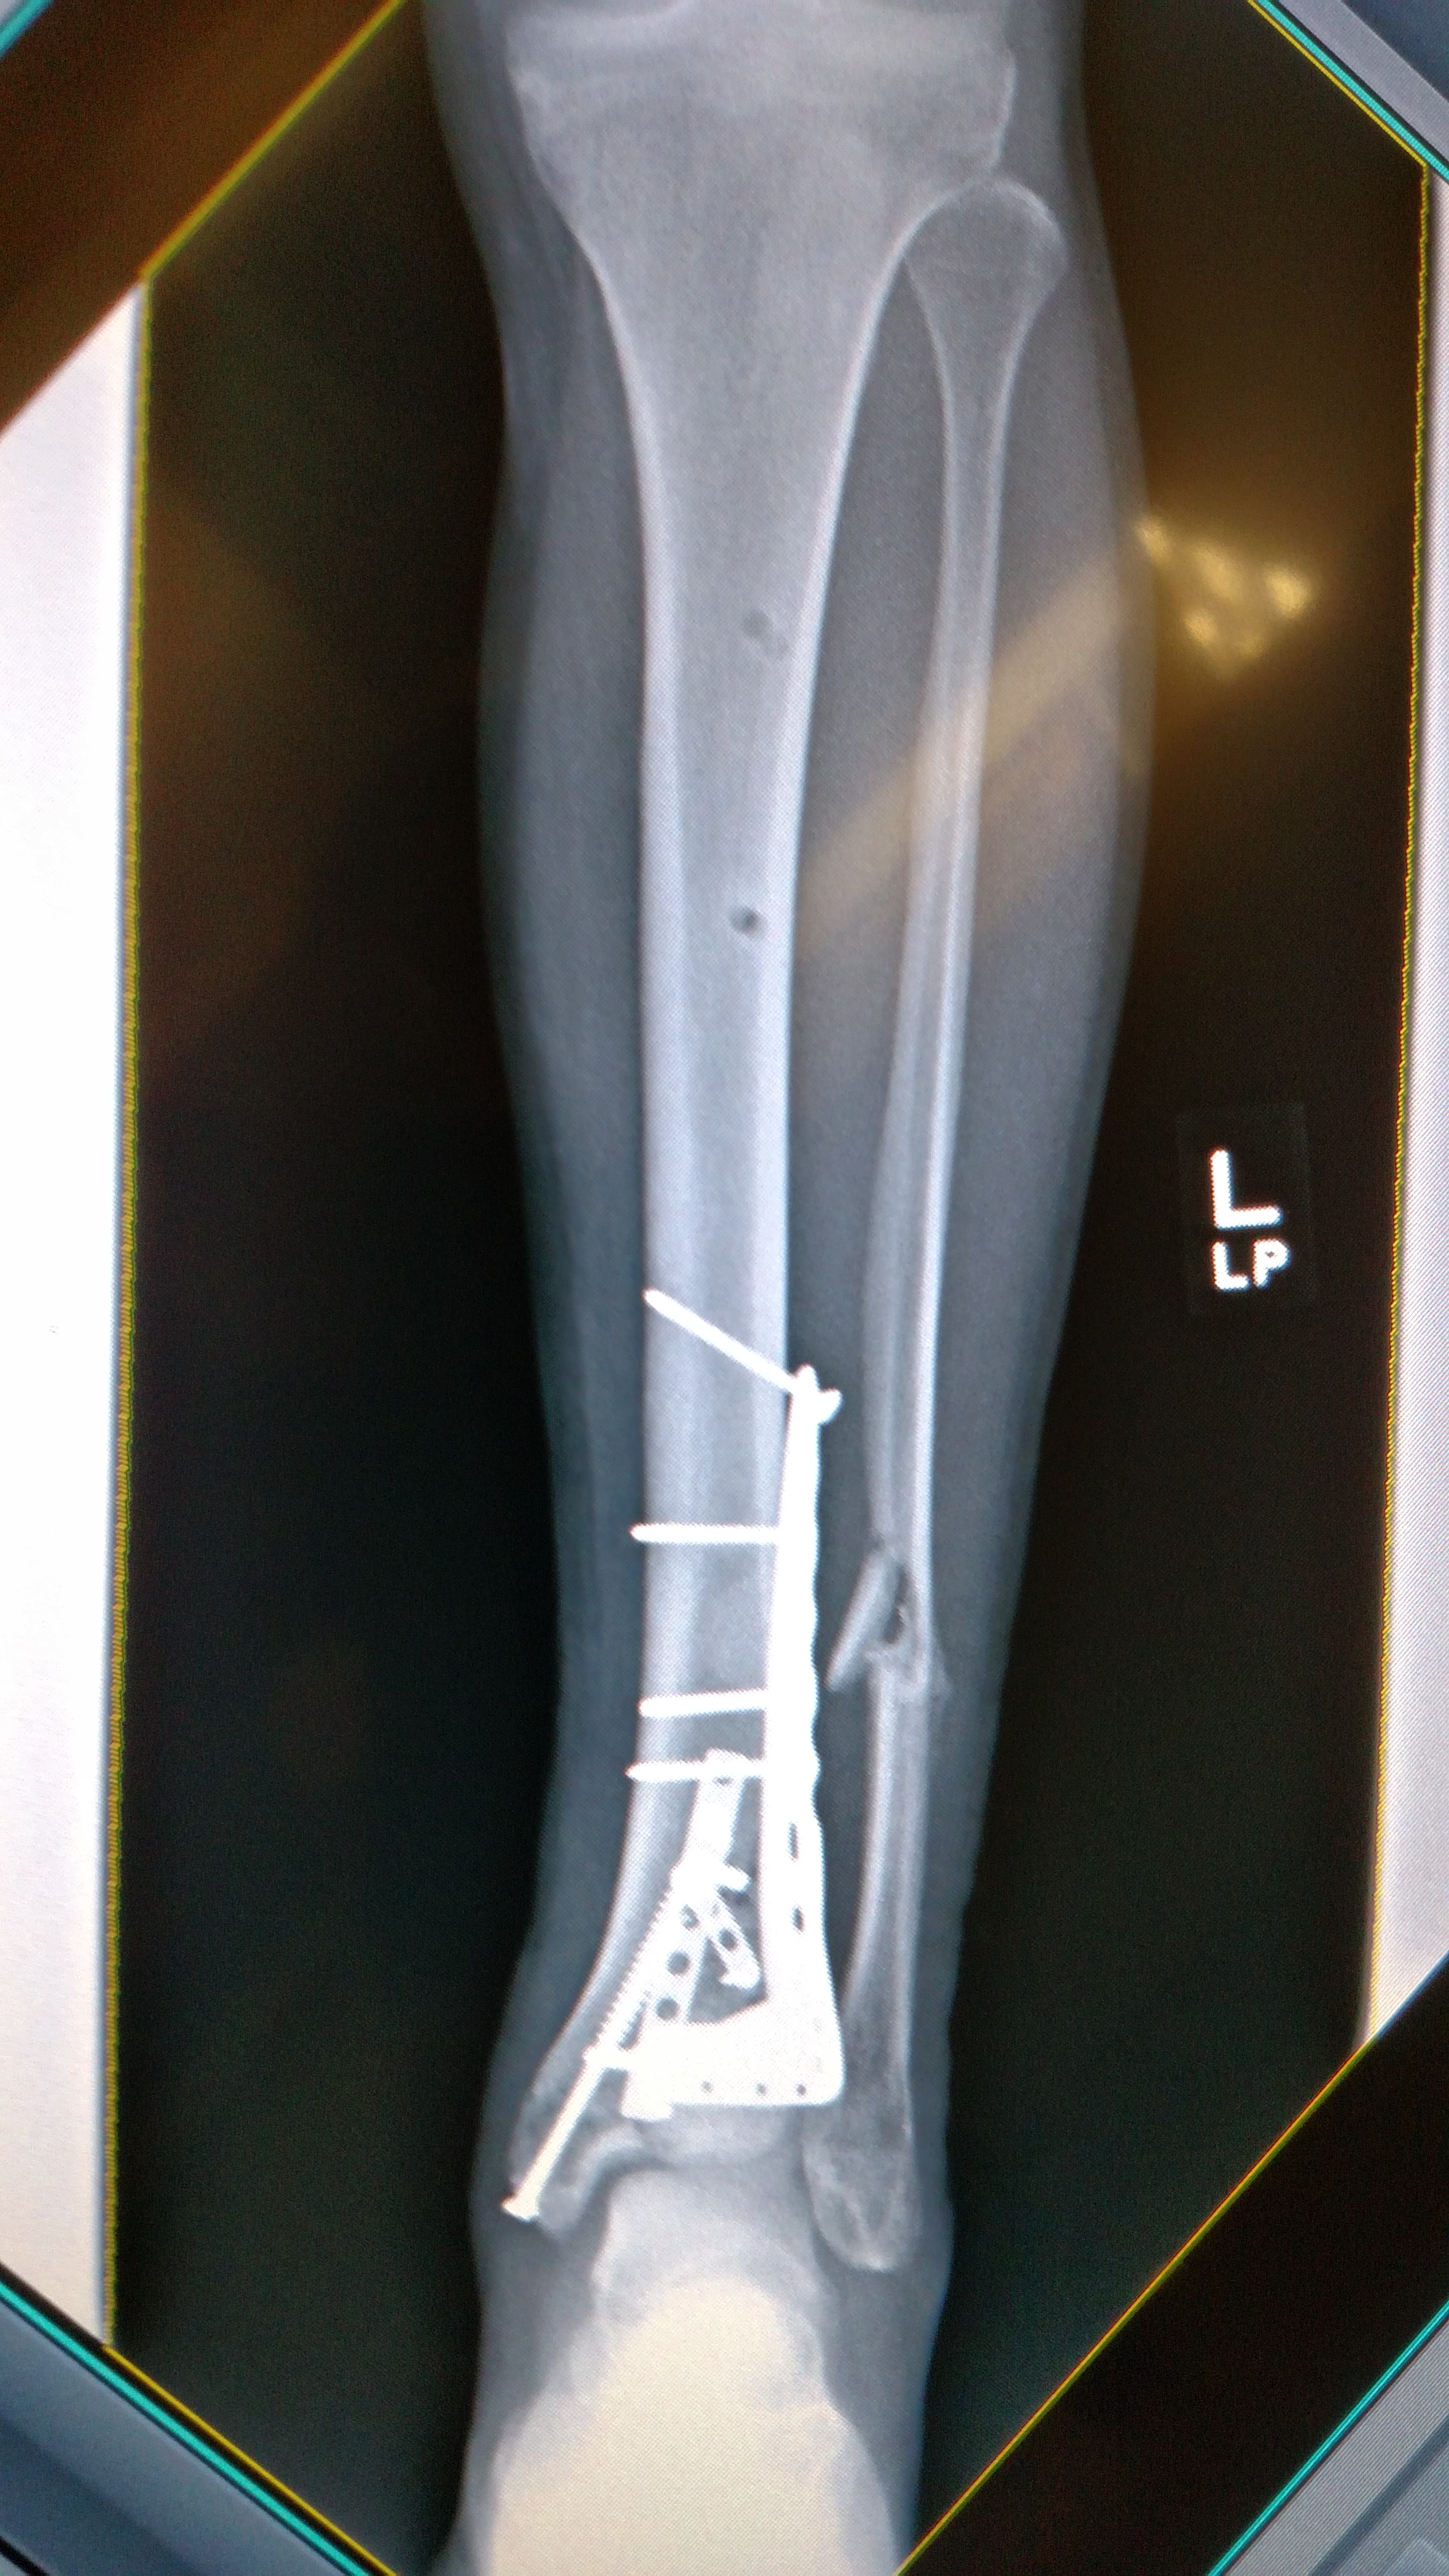

IMG_20150423_105443277 Published August 20, 2015 at 2952 × 5248 in IMG_20150423_105443277 This is where we started. All the hardware is still in there